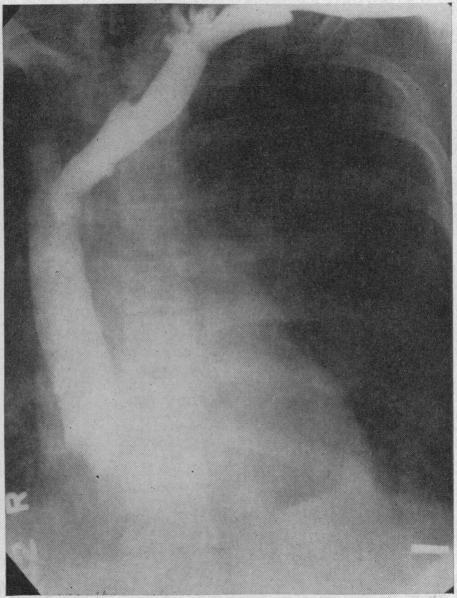

Angiocardiography is indicated in selected cases of heart disease in which a definite diagnosis cannot be made by ordinary methods or in which there is reasonable expectation that the information so obtained may influence the treatment of the patient. Whenever possible, angiocardiography should be done in conjunction with cardiac catheterization. The main indication for angiocardiography is cyanotic congenital heart disease; primarily those cases in which there is a right-to-left shunt. Angiocardiography is occasionally of value in diagnosis of other types of congenital heart disease and in acquired heart disease.